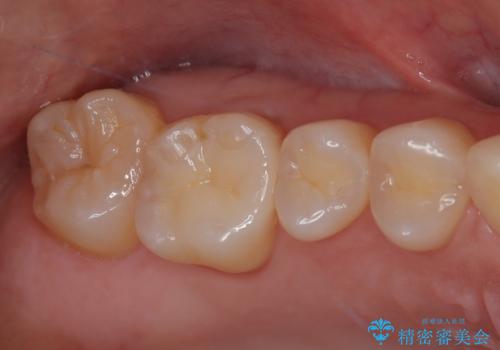

見た目、機能面共に大変喜んでいただきました。

歯と歯の間の虫歯をコンポジットレジンや保険のメタルインレーで治すと段差ができたりして清掃性が悪くなるので、セラミックインレー修復やゴールドインレー修復などの適合の良い詰め物で治療することをオススメします。